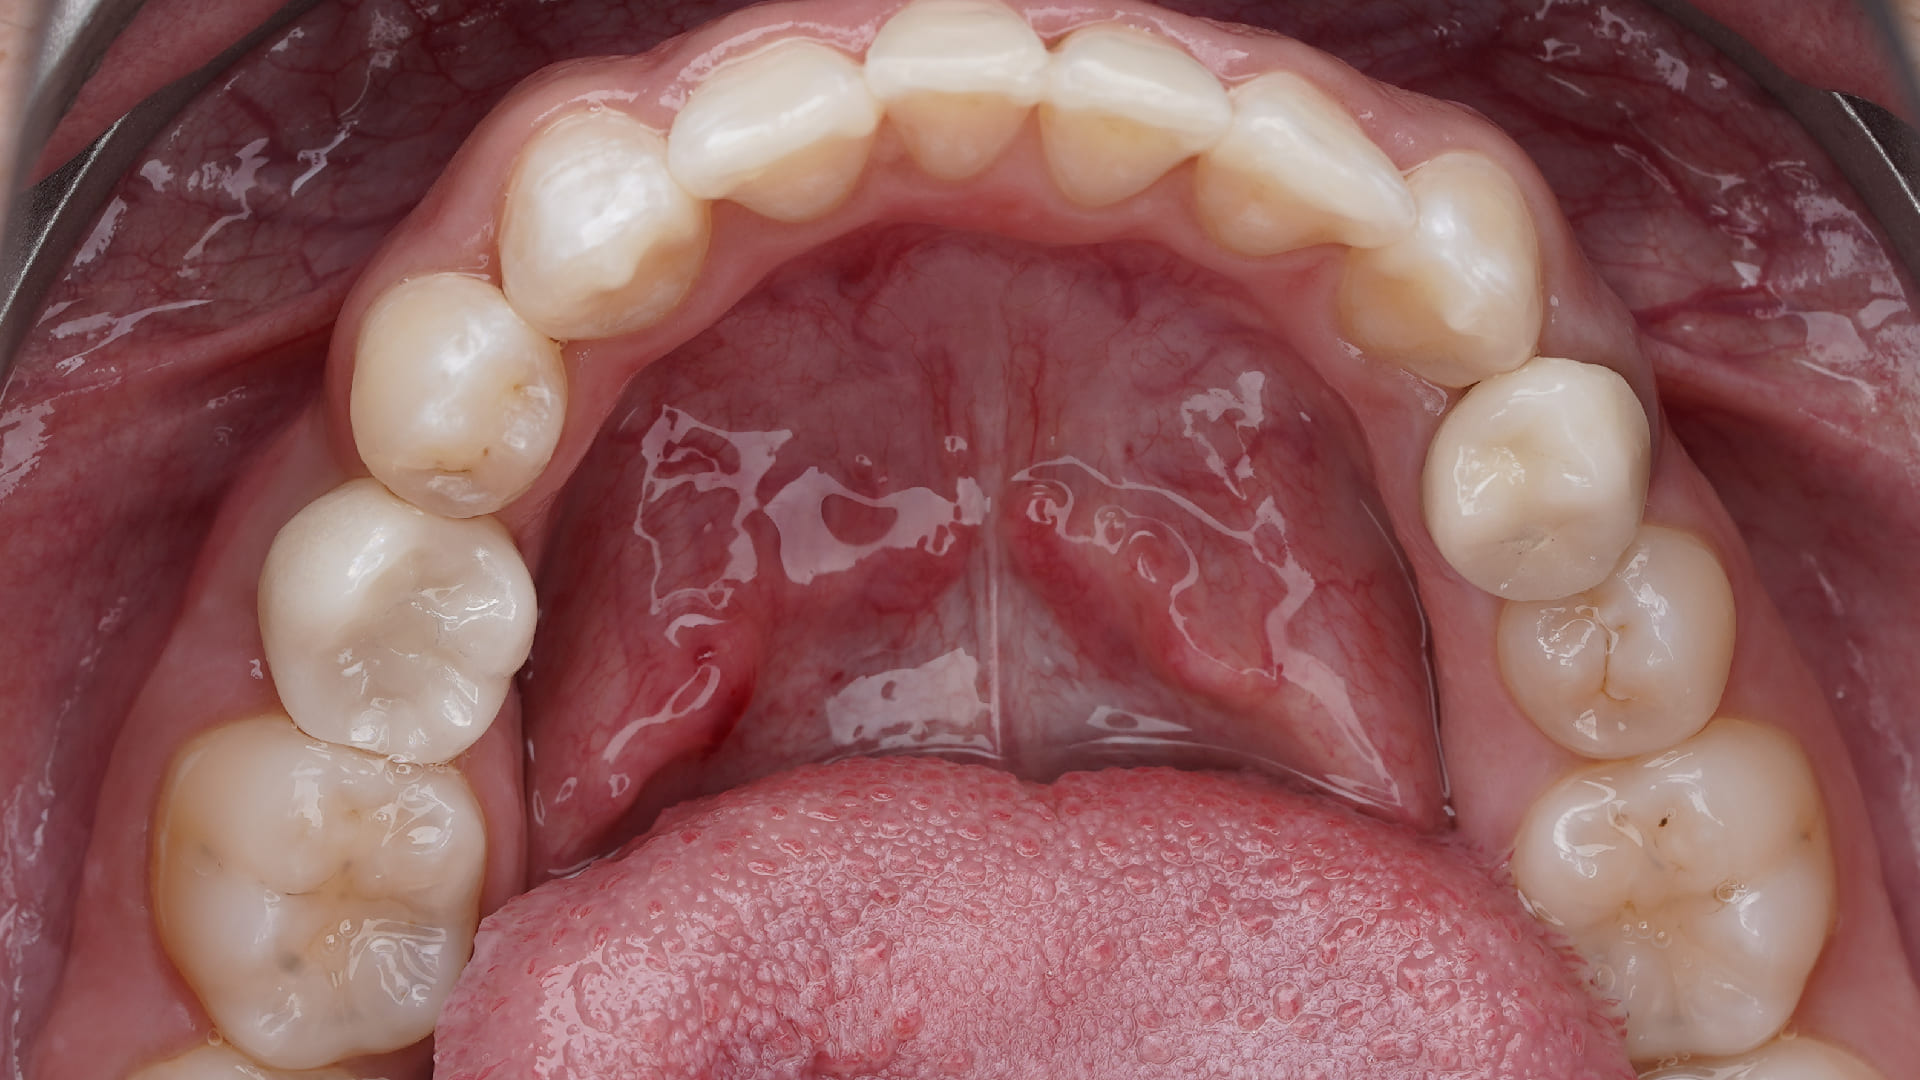

Posterior Immediate Implants.

Customized healing in the posterior sites

CLINICAL CASES